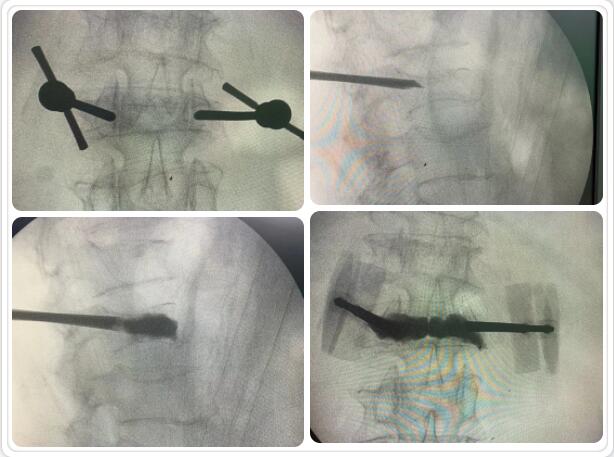

經(jīng)皮椎體球囊擴張成形術(shù)是目前臨床治療骨質(zhì)疏松性胸腰椎壓縮骨折的常用方法。椎體成形術(shù)是在局部麻醉和透視下在骨折椎體內(nèi)插入一根或兩根長針,通過長針往椎體內(nèi)注入骨水泥固化骨折部位,維持椎體穩(wěn)定,防止傷椎進一步塌陷;同時骨水泥固化過程中發(fā)熱導致周圍組織壞死、感覺神經(jīng)末梢毀壞, 產(chǎn)生良好的鎮(zhèn)痛作用。通常術(shù)后第二天即可在支具或腰圍保護下下床活動,大大提高了生活質(zhì)量。該微創(chuàng)手術(shù)具有手術(shù)創(chuàng)傷小、起效迅速、安全性高等特點,目前已被廣泛應用于臨床。

椎體成型(微創(chuàng)手術(shù))過程